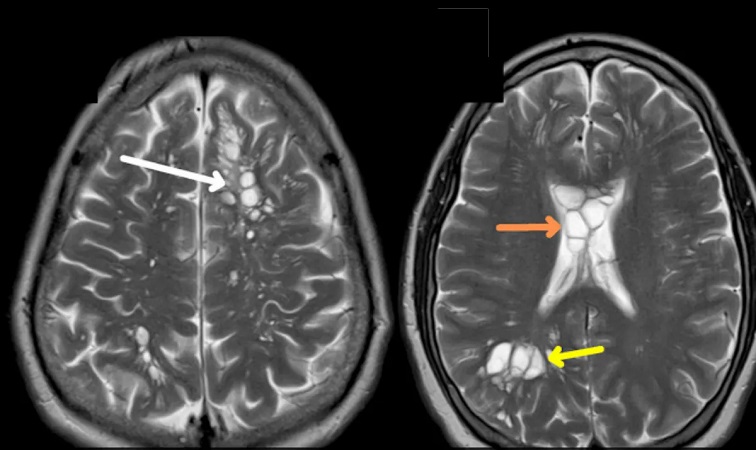

মাইগ্রেনের সমস্যা অনেকেরই আছে। কিন্তু সেই রোগ সারাতে গিয়ে এক ভয়ঙ্কর সমস্যা দেখলেন চিকিৎসকরা। রোগীর সিটি স্ক্যান ধরা পড়ে ওই ব্যক্তির মাথায় একাধিক সিস্ট রয়েছে, যা শূকরের টেপওয়ার্মের কারণে তৈরি হয়েছে।

প্রতিবেদনে বলা হয়, হাসপাতালে গেলে দ্রুত সিটি স্ক্যান করার সিদ্ধান্ত নেনে চিকিৎসকরা। সেখানেই দেখা যায় ওই ব্যক্তির মাথায় একাধিক সিস্ট রয়েছে। যা শূকরের টেপওয়ার্মের কারণে তৈরি হয়েছে বলে নিশ্চিত হন চিকিৎসকরা।

চিকিত্সকরা জানান, পরজীবী সংক্রমণ নিউরোসিস্টিসারকোসিস রোগে আক্রান্ত ওই রোগী। বৈজ্ঞানিক পরিভাষায় শরীরের বিভিন্ন অঙ্গে সংক্রমিত করে।